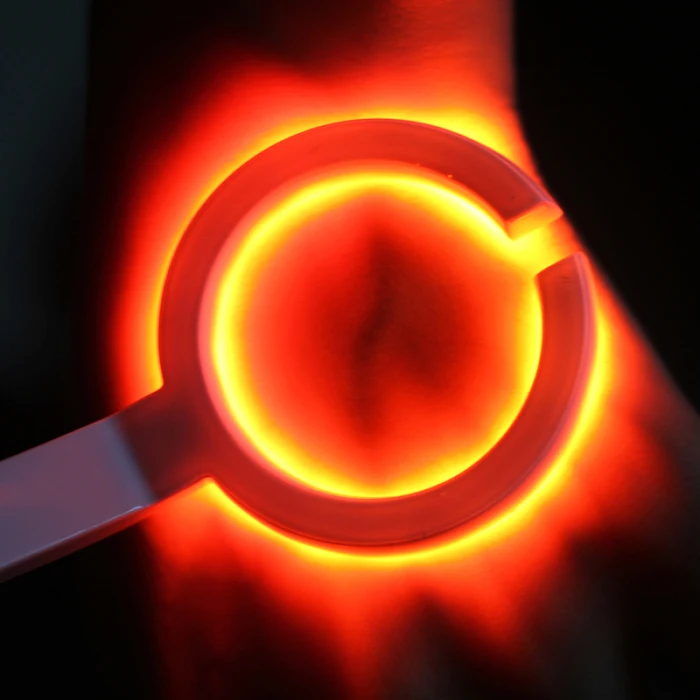

Взрослая детская визуализация инфракрасный васкулярный IV вены Finder Transilluminator вены просмотра TN88

Наше портативное устройство для просмотра Вены-Доступный портативный обнаружитель вен для общего доступа вены у взрослых и детей.

Он используется для эффективного доступа IV в аварийной медицине.